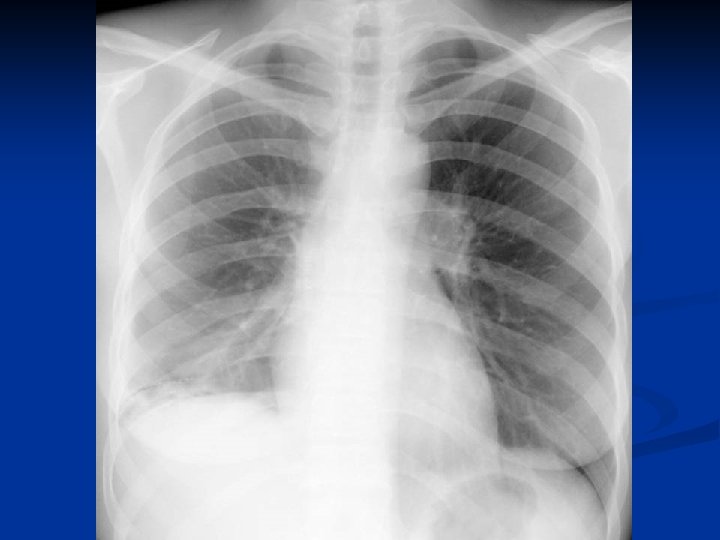

Metode de diagnosticare